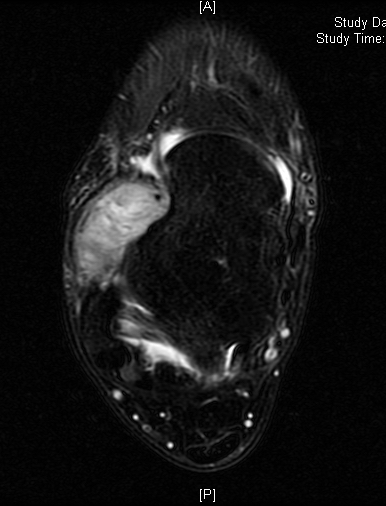

Shows multiloculated, heterogeneous mass.

“Triple Signal Intensity sign”; hypointense, isointense and hyperintense with fat on T2 – weighted MRI imaging. This sign is present in 30 to 50% of the cases. (Fig.3)

Under contrast enhancement Synovial Sarcoma appears heterogeneous and demonstrate areas of nodular enhancement.

In approximately 30% of cases a multiple vascular cannel may be identified

Synovial sarcomas may have a cystic appearance and are often mistaken for ganglion cysts especially those adjacent to tendons and in the foot and ankle.